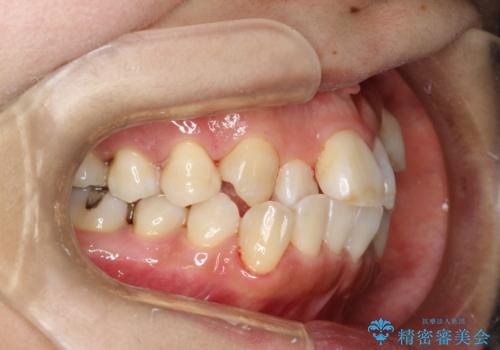

プラーク(細菌の塊)や歯石がたまると歯の表面はザラつきいてきます。そのザラつきは歯周病や虫歯菌の棲家となります。そのまま放置すると、歯肉が腫れてきたり、歯肉から出血したり、口臭が強くでたりします。とくに歯肉の境目は、歯磨きで汚れを除去することが難しく、プラーク(細菌の塊)や歯石が溜まりやすい場所です。

歯並が、がたついている場合はなおさら汚れが溜まりやすいです。矯正治療前や矯正中、定期的にPMTCをすることで、矯正治療中の歯肉トラブルを防ぐことにつながります。